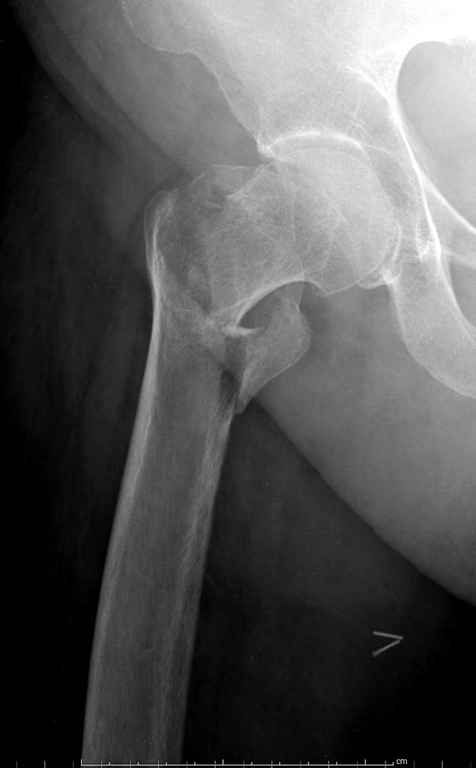

До выхода блокируемых гвоздей для фиксации косых подвертельных переломов в основном применяли Blade Plate. За счет уникальной конструкции создавался Fixed Angled Device, который соединял головку с диафизом, минуя зону перелома.

За счет особой конструкции клинка и подпорки (buttress) в диафиз создавалась стабильность, и предупреждалось скольжение по линии перелома. Перпендикулярная поверхность клинка предупреждала сгибательные и разгибательные смещения, и в сравнении с круглым винтом редко происходило прорезыванием.

Вашему вниманию представляется похожий случай, пациентке 70, осложнился в течение одного месяца после операции. Ревизия с заменой сустава, кабельная фиксация на трохантер. При установке в дистальном диафизе обнаружен тонкий кортикальный слой и сделана профилактика от возможного перелома аллографтом.